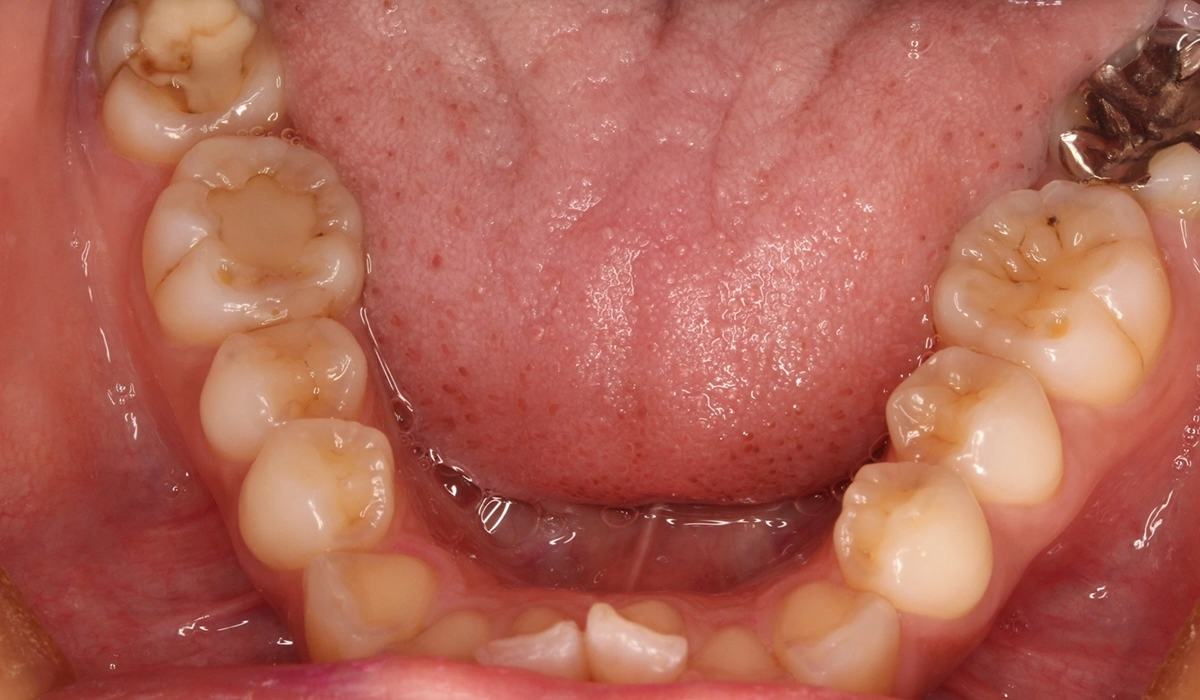

術前:下顎

術後:下顎